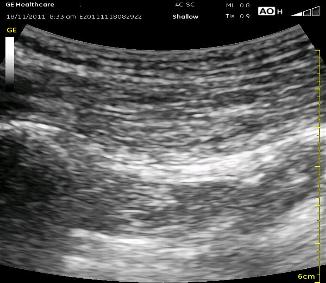

The following ultrasound pictures demonstrated the difference in view when the probe is initially placed and then ‘rocked’ to slightly to see the sciatic nerve at a 90 degree angle to the probe. You can see the GT coming in at the left with darkness below it, and the IT can barely be seen on the far right.This is opposite to the cartoon drawings above. Look closely in the center from top to bottom to see if you can distinguish the layer of subcutaneous fat from the GM just below. Look deeper to notice the line (best seen in the first picture) of the deeper layer of the GM which ‘dips down’ a little between the GM and IT. This is the most critical cue to note. That line should contain the Sciatic Nerve, and deep to it is the QF. Once you have noted these findings, you should ‘rock’ the probe slightly to bring the Sciatic Nerve into better view. Note the bright areas deep to the QF toward the left and bottom of the picture. Those are not your targets. Now that you can appreciate the difference in the appearance of these various tissue layers, you should not be pulled off course. Remember, you are looking for a distinct border between the muscle fibers of the GM and QF.